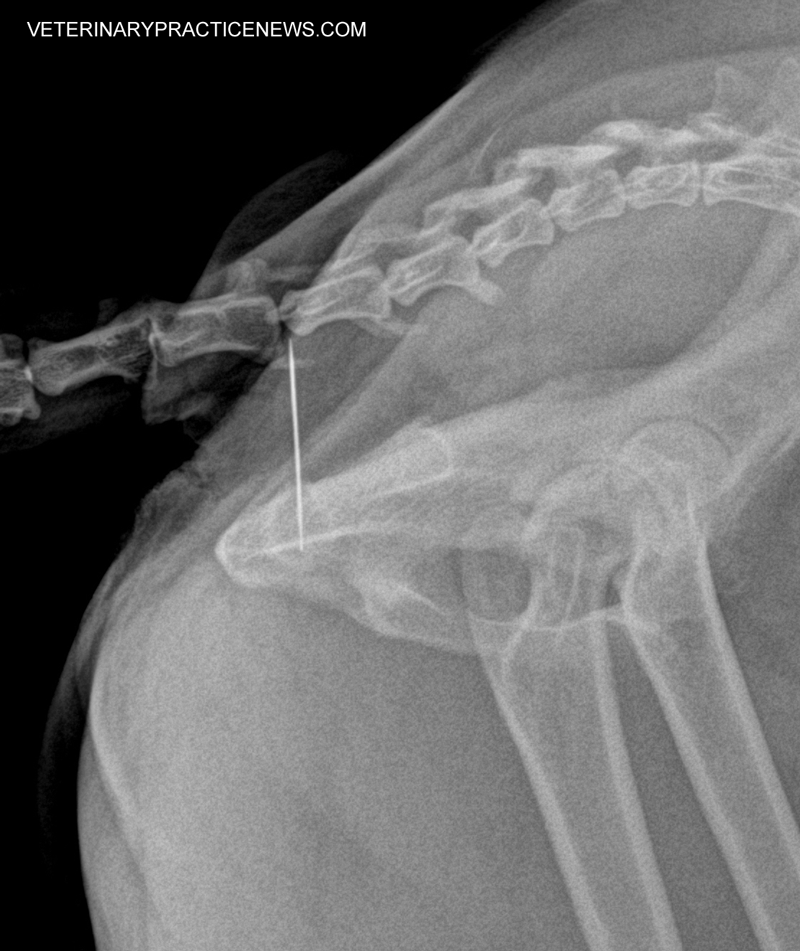

Needle in a Hay Stack (and Rabbit's Mouth)

Rabbit with Needle in Mouth

Photo courtesy Tracy Eichenseer, DVM, and Mariah Covey, DVM, Kryder Veterinary Clinic, Granger, Ind.

Upon examination, an 18-month-old rabbit named Winfrey was thought to have a dental abscess. It was in the right back corner of her mouth and extended to the right side of her face.

Survey X-rays showed a sewing needle. We surgically prepped the area on the side of her face, palpated the area, performed a cut-down and extracted the needle in one piece.

Her owners keep Winfrey in a finished basement, a former sewing room. Since rabbits eat hay, we think Winfrey found the "needle in a haystack."